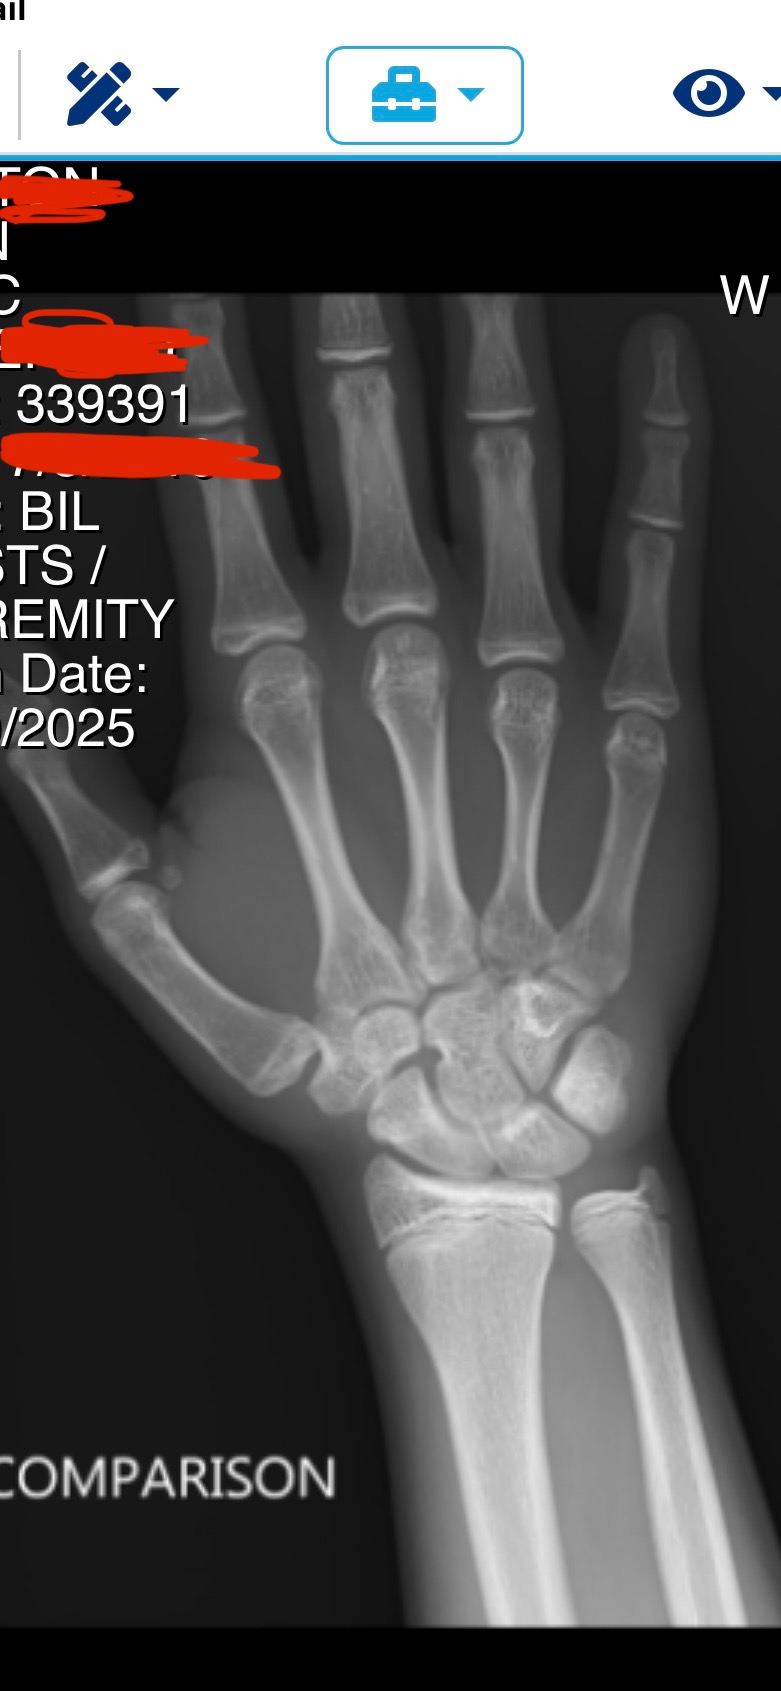

i’m 15 1/2, my plates are beginning to close, and i don’t want to be stuck in this fucking body forever, i’d do anything for aromasin or gh rn, is it truly over for me, if i stick to the gym ill just be a short stubby guy who no woman would want to approach. then again i could find a woman who truly loves me regardless of my height, but thats highly unlikely.:feelswhy: